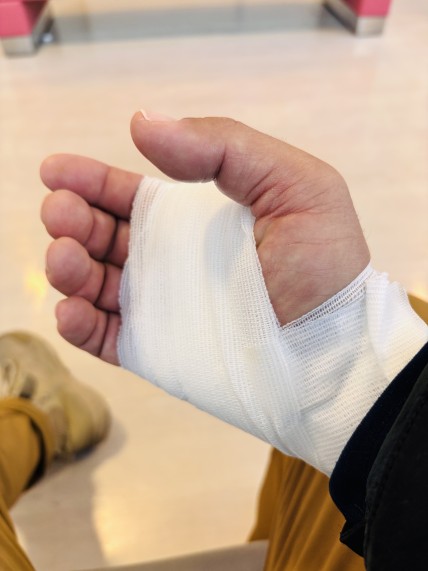

とりあえずフックを確認。

……これは無理。

セルフ対応、即断念。

船を接岸してもらい、自分だけ下船。

そのまま病院へ直行。

待合室では、ジグを握りしめたまま。

周囲のおばちゃんたちからは

「それすごいねぇ!」と謎の注目を浴びる。

レントゲンで状態確認後、

部分麻酔 → 切開 → グリグリ。

無事、摘出完了。